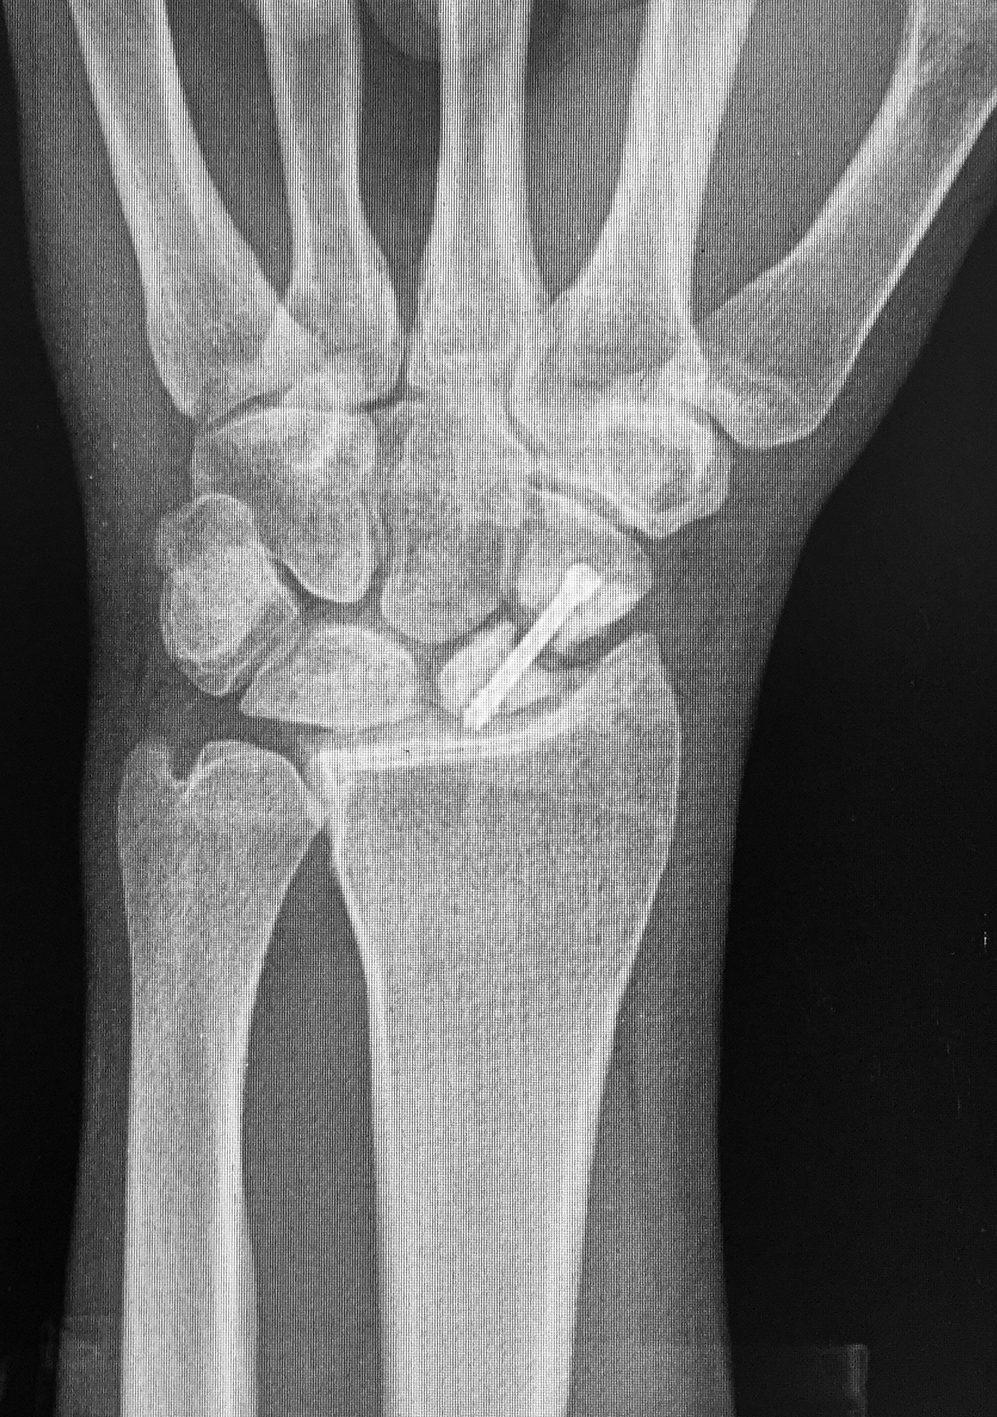

Efectuamos un abordaje volar dado que conserva la vascularización dorsal, permitía la visualización directa del foco, movilización de los polos y manejar la deformidad en joroba mediante el injerto trapezoidal (1)(11)(12). Nos centramos sobre el tendón palmar mayor, efectuando una incisión curvilínea dirigida hacia el tubérculo del escafoides. Se protegió la rama sensitiva cutánea del nervio radial y disecamos el plano superficial incidiendo la cápsula longitudinalmente sobre el eje del escafoides. Se reflejó la cápsula, se identificó el polo distal y proximal colocando dos agujas de Kirschner, a modo de joystick. Cureteamos el foco con una fresa (Figura 1). Dejando el escafoides, extrajimos un injerto cortico-esponjoso trapezoidal de cresta iliaca (Figura 2). Volviendo a la mano, distrajimos los fragmentos escafoideos y colocamos el injerto, con su base en situación volar, para extender el escafoides (1)(5)(12)(13). Colocamos otra aguja de Kirschner retrógrado como guía, y tras medir y mechar, colocamos un tornillo de compresión interfragmentaria (11), para proceder posteriormente a cerrar la cápsula y los planos superficiales. Se colocó una inmovilización con férula de yeso, incluyendo el primer dedo, que mantuvimos durante 4 semanas.

Se efectuaron radiografías dorso-palmar, lateral pre y post operatorias. Al final del seguimiento se evaluó la consolidación mediante radiografías. Se indicó un TC de puño en los pacientes como método de valoración pre operatoria y la RM cuando se sospechó un compromiso vascular del polo proximal para definir técnica quirúrgica.

La evaluación de la movilidad mostró que 5 pacientes (29,4%) tenían la movilidad completa; 11 pacientes (64,7%) la conservaron entre el 75 y el 99 % y un paciente (5,9%) entre el 50 y el 74%. No encontramos asociación estadística entre la movilidad y el retraso terapéutico (p=0,241). (Figura 3) (Figura 4) (Figura 5) (Tabla 1) (Tabla 2).

Figura 3: Caso 9

a) Radiografia de perfil pre-opertaoria

b) TC pre-operatoria. Corte sagital

c) TC pre-operatoria. Corte coronal

d) Radiografías post-operatorias

e) Radiografía de frente, 33 meses seguimiento, pseuodartrosis persistente

f) Radiografía de frente, 33 meses seguimiento, pseuodartrosis persistente

Figura 4: Caso 12

a) Radiografía de frente pre-operatoria

b) Radiografía pre-opertaoria, enfoque de escafoides

c) Radiografía post operatoria

e) 24 meses de seguimiento. Radiografía de frente

f) 24 meses de seguimiento. Radiografía de perfi